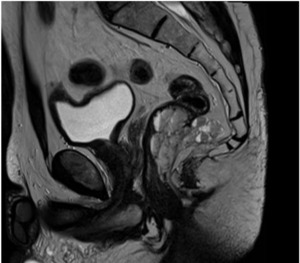

Inhomogeneous signal hyperintensity in T2-weighted sequences with a fluid/fluid level appearance, isointensity signal in T1-weighted sequences, no signal reduction in T1-weighted sequences in opposition of phase in agreement with the absence of a lipid component, no signs of signal restriction in diffusion (ADC 1.6), thin peripheral contrast enhancement, and thin septa in the structure were all features of the MRI. The lesion on the right posterolateral side appeared to affect the muscular coat, extending to the serosa raising suspicion for a teratomatous-type lesion. Following multidisciplinary consultation, surgical excision was planned. A transanal local excision was performed under general anesthesia (Figure 3). The patient’s postoperative course was uneventful, and he was discharged on the first postoperative day. Histopathological analysis revealed an edematous, ulcerated, and chronically inflamed segment of the large intestinal wall, containing lymphatic and intraparietal blood vessel ectasias consistent with hemolymphangioma. No postoperative complications were observed. The patient underwent regular follow-up evaluations, including proctological examinations, CT scans, and MRI studies (Figure 4) every six months for the initial two years, followed by annual assessments. At four years postoperatively, there is no evidence of disease recurrence.